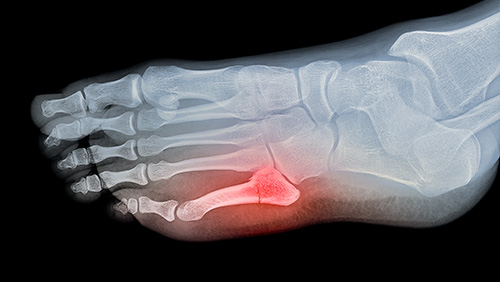

Foot Fractures

Description:

There are 26 bones in the foot and they are vulnerable to break with trauma.

Treatment:

The majority of foot fractures heal by themselves with the use of a walking boot for a period of time and anti-inflammatories. Those fractures with bone ends too far from each other (or too displaced) to heal by themselves will require surgery to be corrected.

Our research:

The heel bone or calcaneum is the largest of the foot bones. We have published the results of a surgical technique that uses minor-incision surgery to fix severe fractures providing faster return to activities. Link to the article